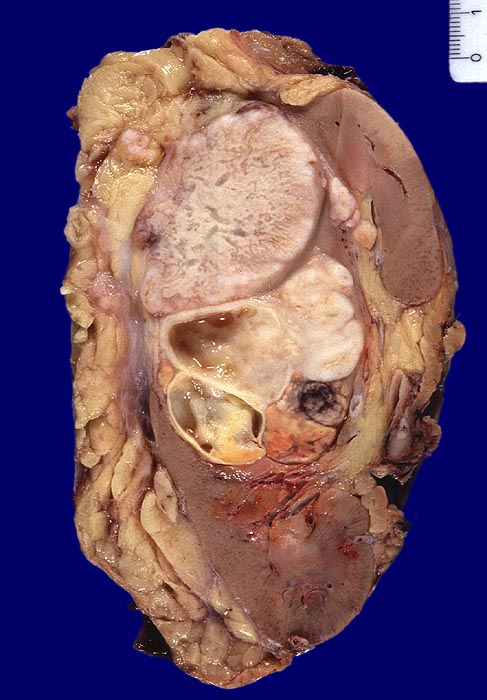

PathoPic – image database / PathoPic ID 4172 - sarkomatoides und teils hellzelliges Nierenzellkarzinom

sarkomatoides und teils hellzelliges Nierenzellkarzinom

Im Nierenunterpolbereich und mittleren Abschnitt ein bunter, teils gelber, teils weisser, teils zystischer Tumor Dm 8,2cm. Fokale kleinere Einblutungen. Der Tumor infiltriert das Nierenbeckenfettgewebe und durchbricht auch die Nierenkapsel mit Infiltration des perirenalen Fettgewebes.

Histologie: Überwiegend wenig differenziertes sarkomatoides und teils hellzelliges Nierenzellkarzinom.